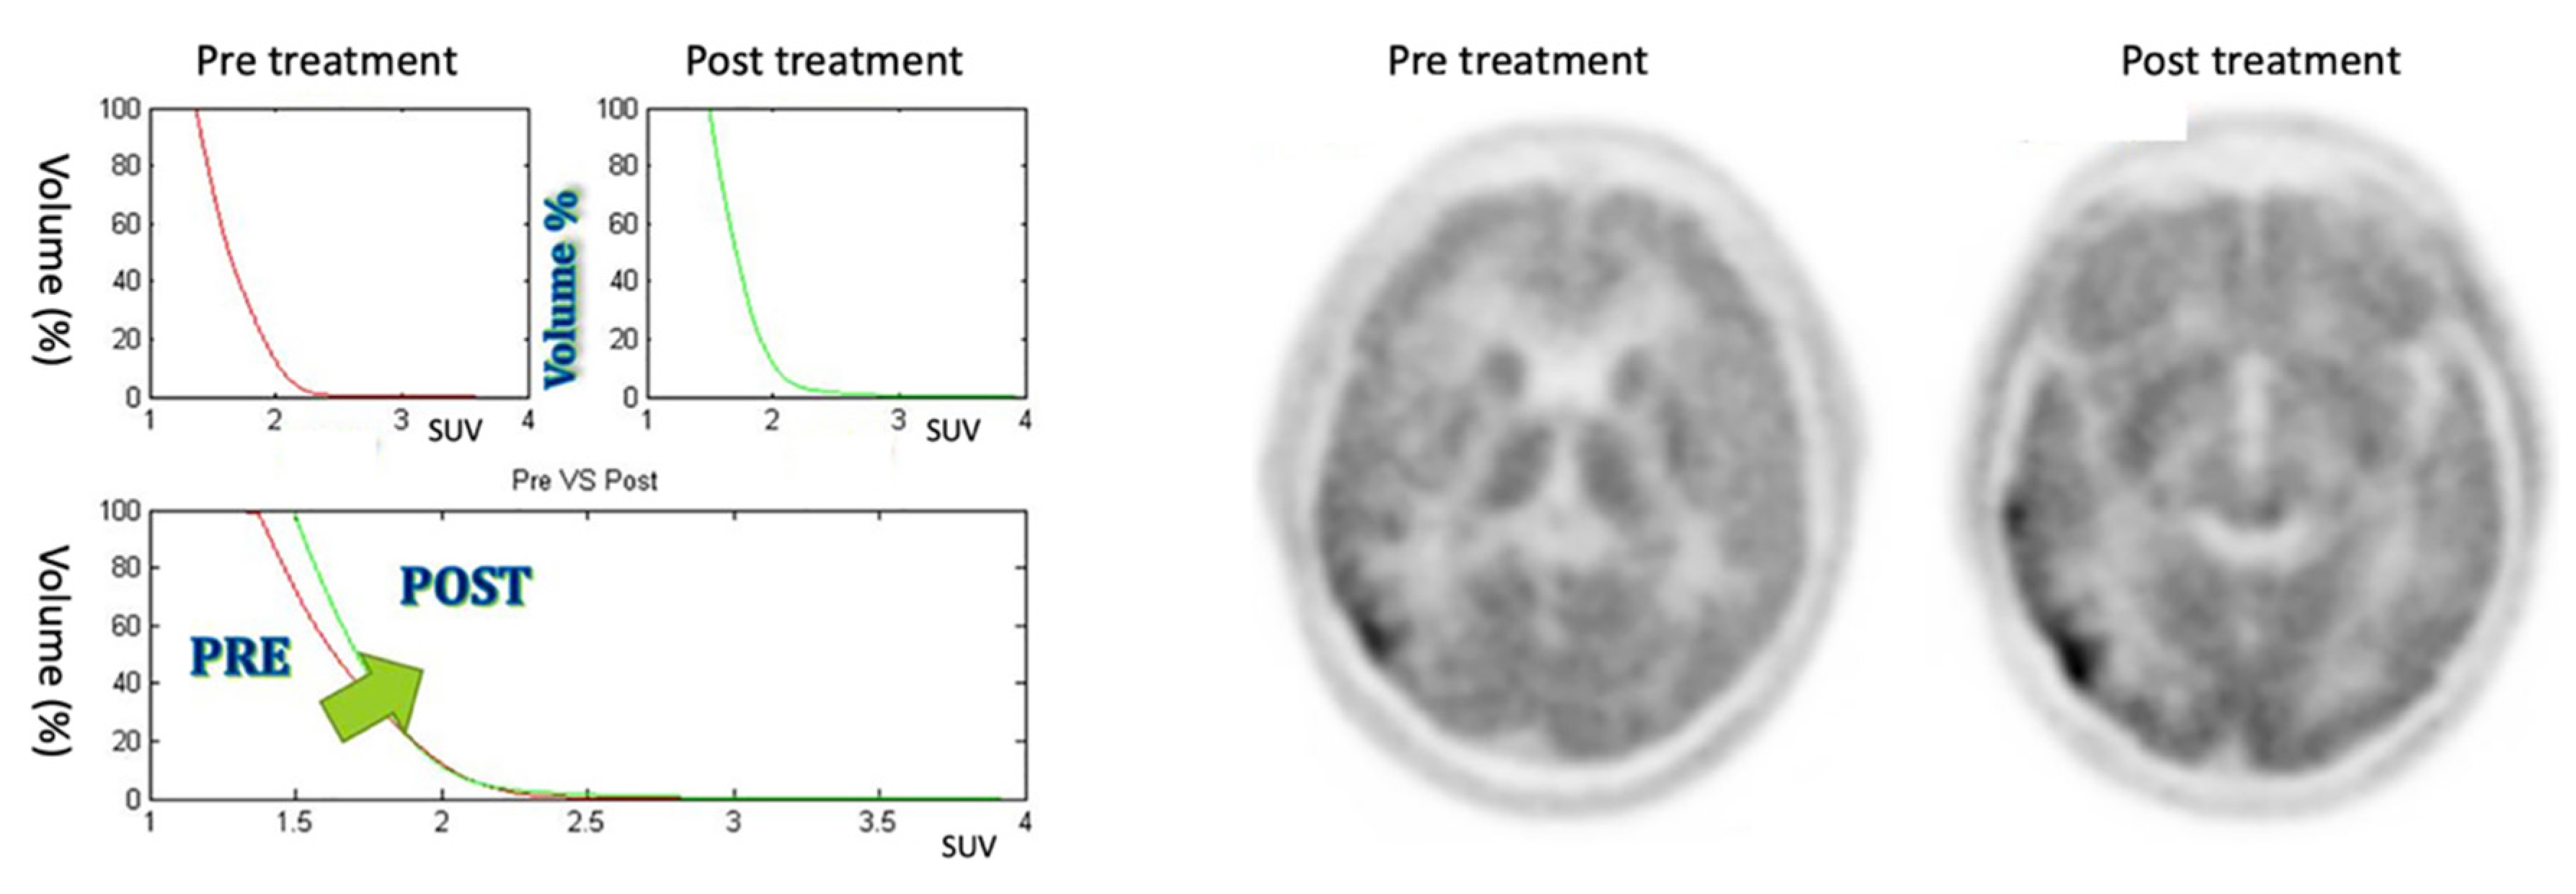

3.2. Stable Response

The five patients included in this class show a AUC reduction of less than 10% and no modification of the CSH between the PET pretreatment and the PET post-treatment, as it is possible to see in Figure 7 (patient #1). Patients included in this category show a moderate response to the therapy.

Figure 7.

On the left: CSH pretreatment (top left); CSH post-treatment (top right); comparison between pre- and post-treatment (bottom) in stable response case: ΔAUC = 2.33%. On the right: PET images of pre- and post-treatment. (For interpretation of the references in this figure legend in colour, the reader is referred to the web version of this article.)